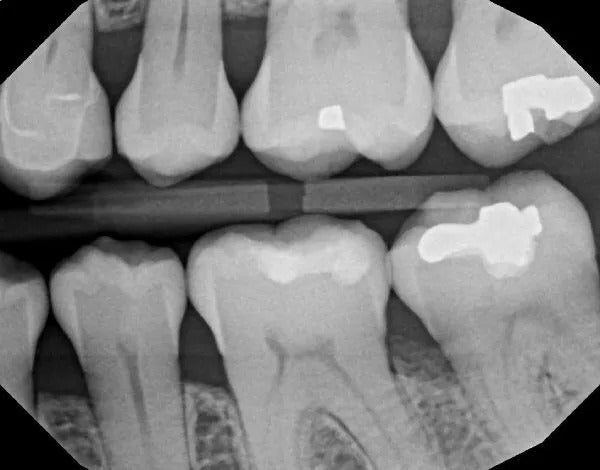

Scaling and root planing is a two-step deep cleaning process used to treat gum disease. Scaling involves removing plaque and tartar from the tooth surfaces, including below the gum line, while root planing smooths the root surfaces, allowing the gums to reattach to the teeth and promoting healing.

Is one of the most effective ways to treat gum disease before it becomes severe. Scaling and root planning is the careful cleaning of the root surface to remove plaque and calculus(tartar) from deep periodontal pockets by smoothing the tooth root surface and removing bacterial toxins it allows your gum tissue to readapt around your teeth.